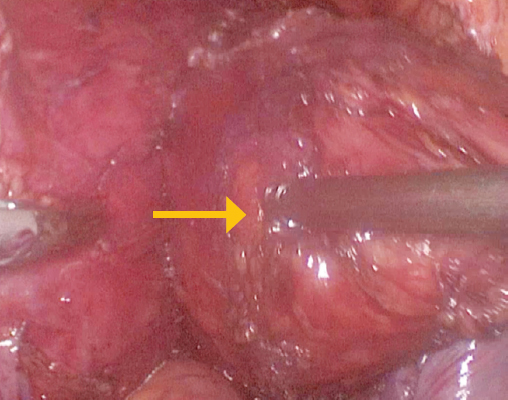

С учетом наличия единичного дивертикула большого объема принято решение о проведении двухэтапного лечения. На первом этапе выполнена лапароскопическая дивертикулэктомия с цистостомией (рис. 6). После операции пациент был выписан в удовлетворительном состоянии с цистостомическим дренажем.

Рис. 6. Пациент И., 37 лет. Интраоперационная картина: этап лапароскопической дивертикулэктомии. Стрелкой указан дивертикул мочевого пузыря / Fig. 6. Patient I., 37 years old. Intraoperative picture: stage of laparoscopic diverticulectomy. The arrow indicates the bladder diverticulum